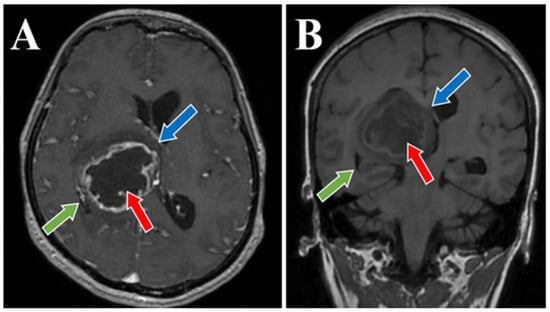

2. Case Presentation